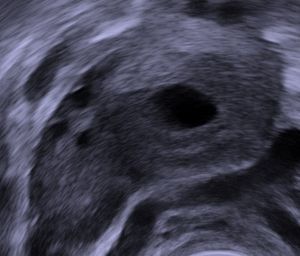

황체는 월경 주기 또는 발정 주기의 황체기에 난포로부터 생성되는 구조이다. 배란 후 난포가 변형된 것으로, 수정 여부에 따라 프로게스테론 분비 지속 여부가 결정된다. 난자가 수정되지 않으면 퇴축하여 백색체가 되지만, 수정되면 임신 유지를 위해 프로게스테론을 계속 분비한다. 황체는 프로게스테론을 분비하여 자궁내막을 유지하고, 릴랙신을 분비하여 분만에 기여하며, 카로티노이드를 포함하여 노란색을 띤다. 황체낭종과 같은 병리가 발생할 수 있다.

보통 난소 안에서 황체의 크기는 매우 크다. 사람에서 황체의 지름은 2 ~ 5 cm 정도이다.[23]

황체낭종은 황체 안으로 출혈이 지속되어 생긴다. 저절로 회복되는 경우가 많다.